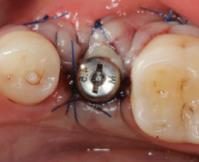

诊断:35牙牙松动。 治疗:拔除患牙,即刻种植。 手术记录:常规消毒铺单,局部浸润麻醉,于35牙牙位行横行切口,骨膜剥离器剥开黏骨膜瓣,显露术野。拔除松动牙,生理盐水冲洗冷却下,球钻定位,植入种植体,旋入愈合帽。 术后拍片,种植体方向好。10天后检查,伤口初步愈合。